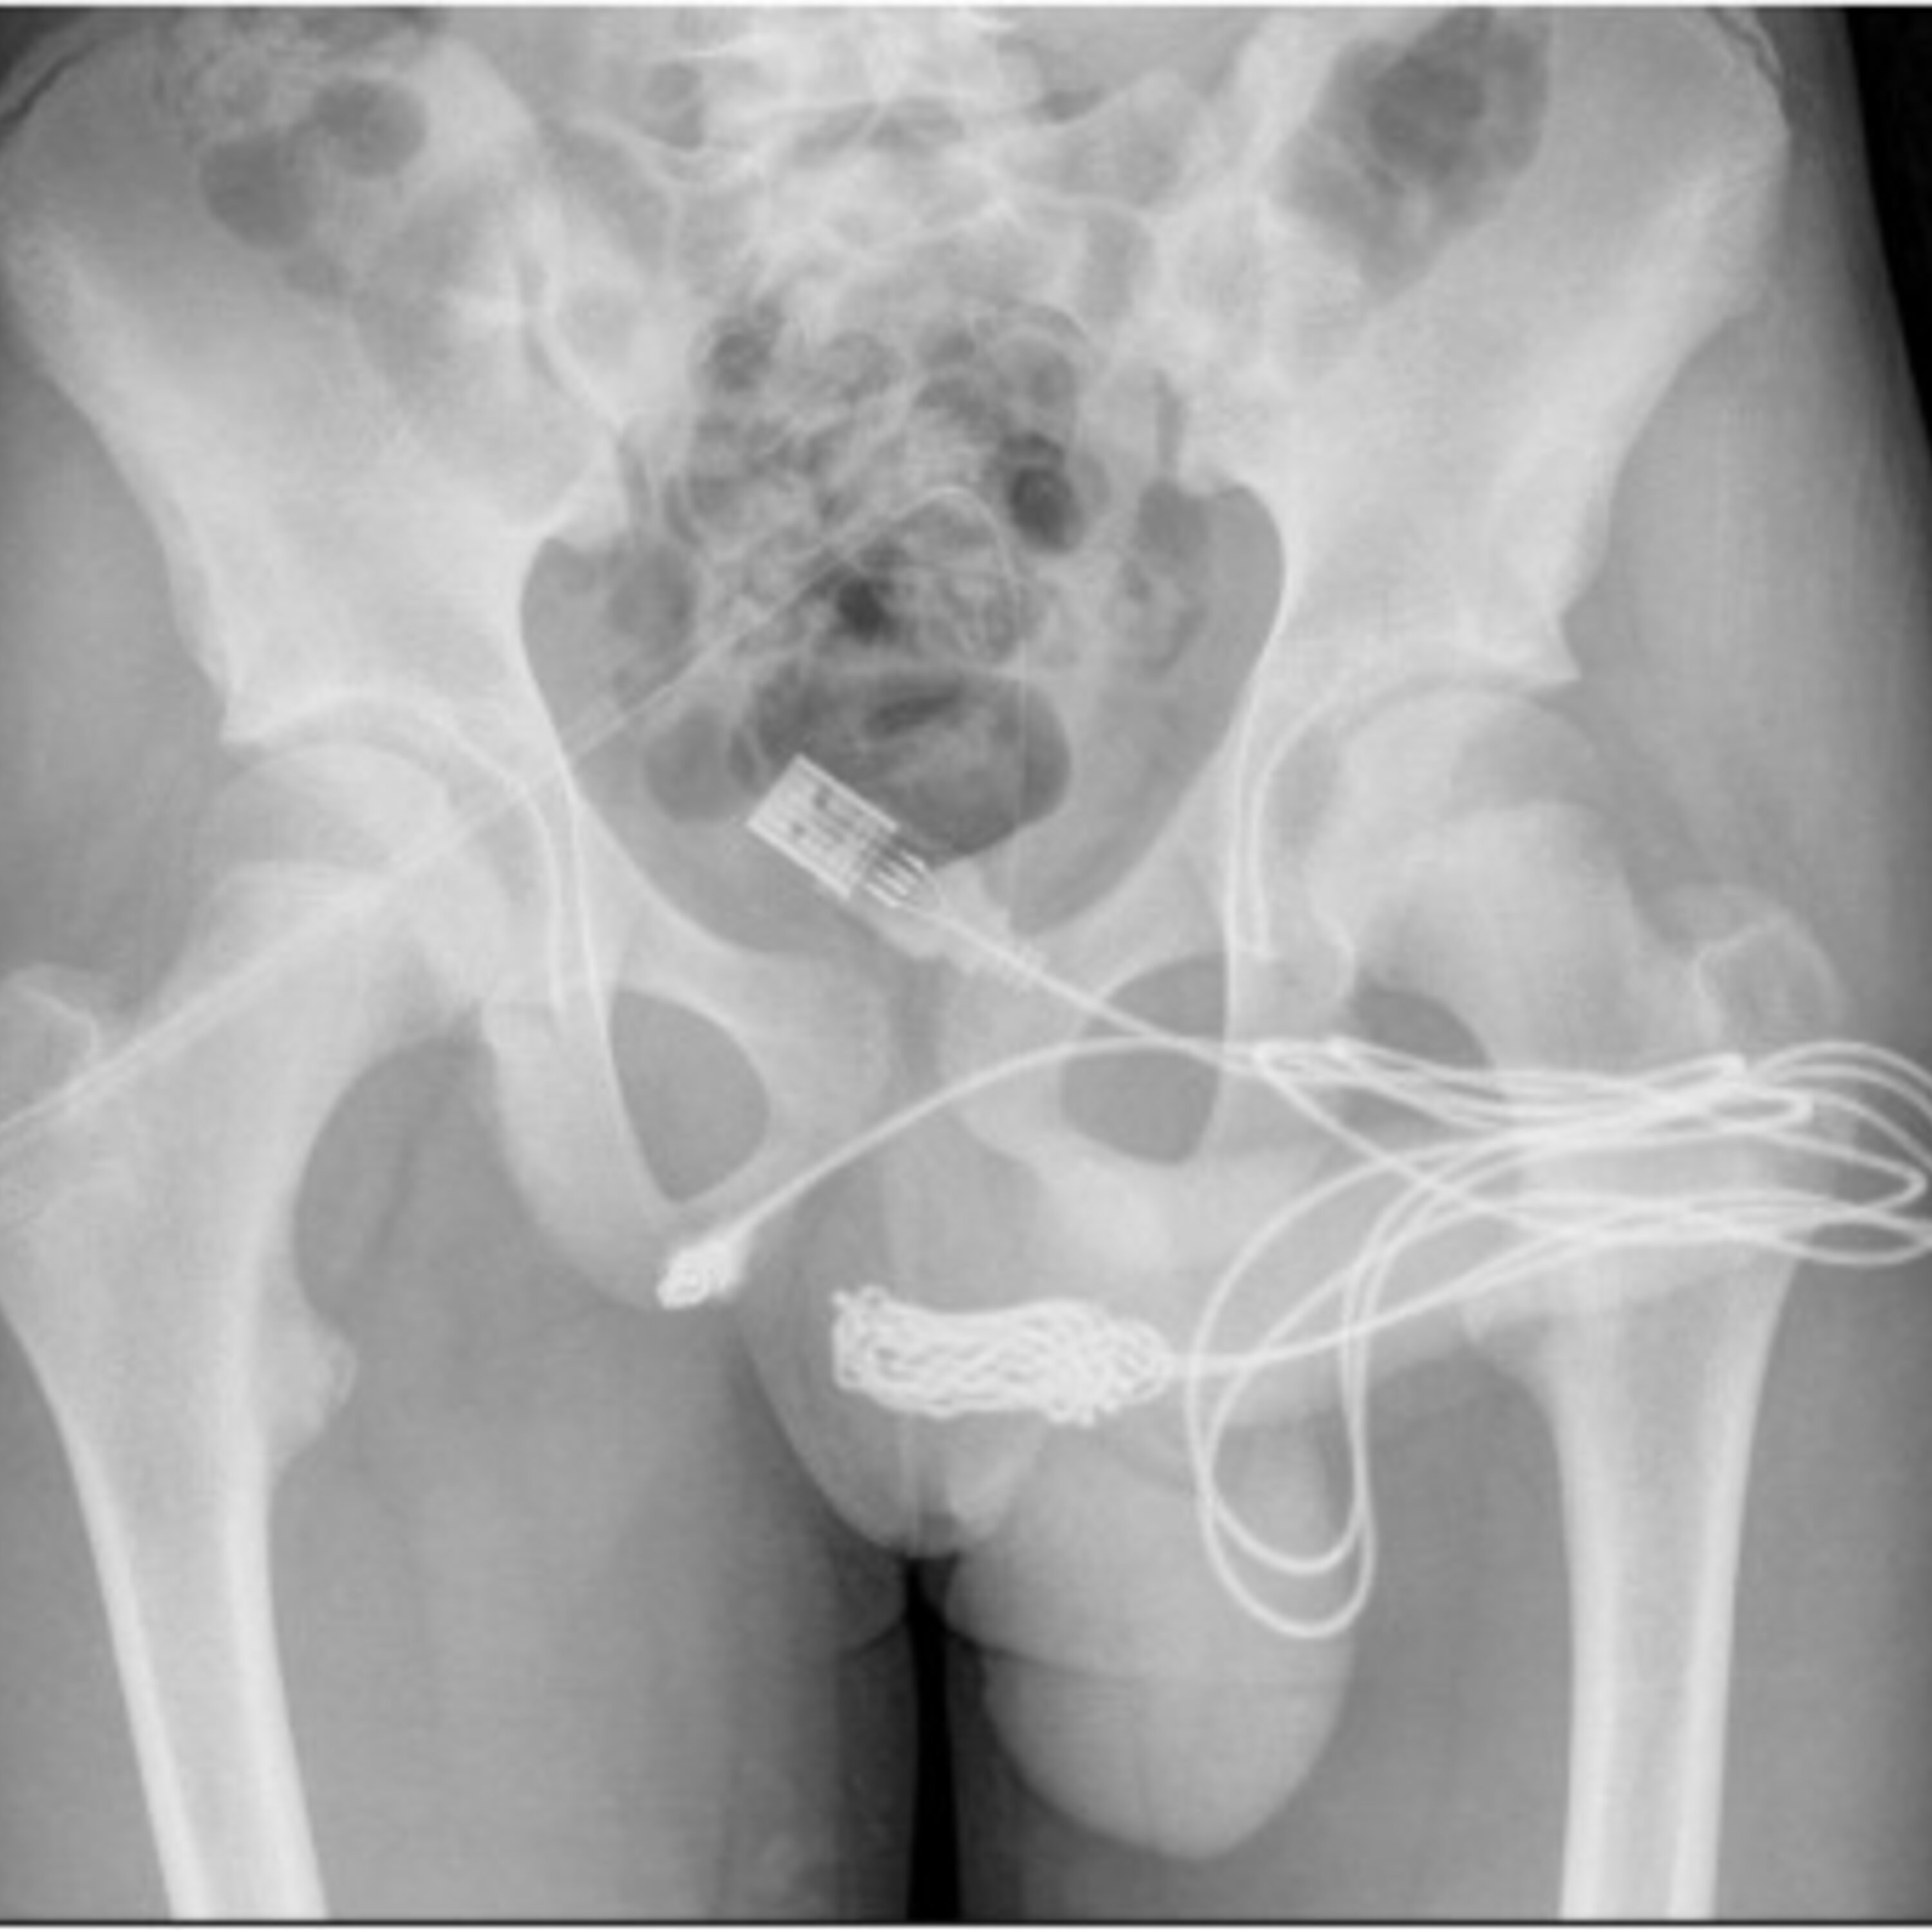

Today: Quitting your job in a blaze of glory, The Emmy's were handed out last night, Sending money to your kid's school, A Lunchables shortage, A teen who shoved a USB cable up his urethra, and predicting the outcome of today's Federal election.